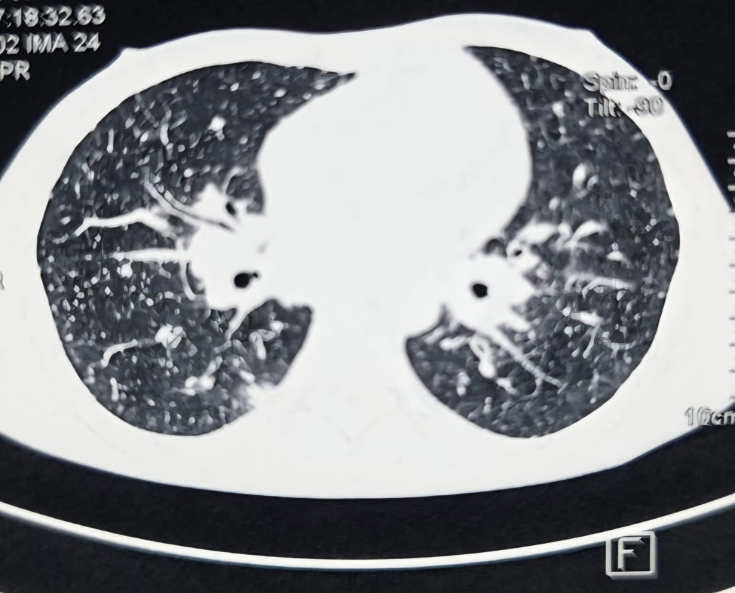

Contrast-enhanced CT thorax revealed (Figure 1): Multiple enlarged mediastinal and right hilar lymph nodes (largest 4.8 × 2.5 cm) along with bilateral lower lobe consolidations & minimal bilateral pleural effusion.

Axial contrast-enhanced CT image demonstrating multiple enlarged mediastinal and right hilar lymph nodes, along with bilateral interstitial nodular changes.